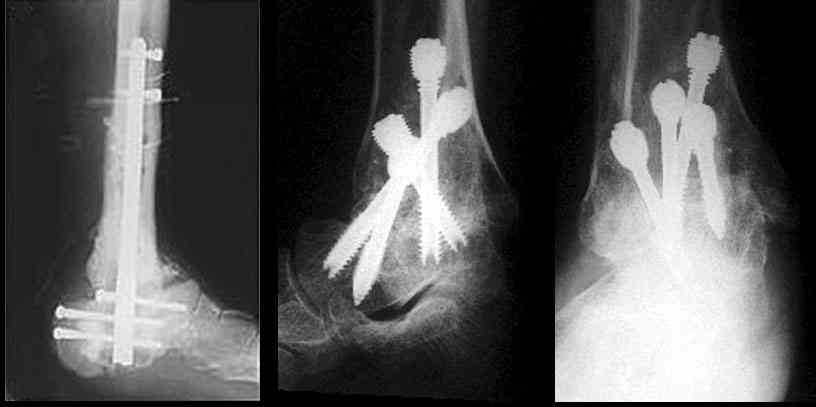

Существуют специальные системы для артродеза голеностопного сустава. См. приложение

Уважаемый А.Семенистый. Складывается впечатление, что вы выполнили трехсуставный артродез, уж больно длинные блокирующие винты. Не мешают ли они пациентке при ходьбе?

Да конечно винты длинноваты! Мешают ли ходить? Во всяком случае субьективно пациентка удовлетворена. Ходит, естевственно, хуже чеи до травмы, но намного лучше, чем до операции.